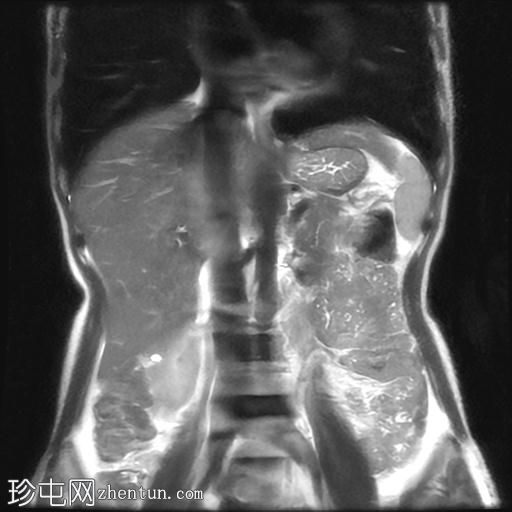

冠状位T2加权像

脂肪抑制像

该宫颈癌体积较大,局部晚期,大小为22 x 40 x 42 mm,起源于宫颈左后外侧壁,向下延伸至阴道上三分之一处,位于宫颈中后外侧壁。

病变还累及左侧前外侧的宫旁组织。

影像学检查结果提示,根据 FIGO 分期系统,该患者为宫颈癌 IIIC1 期。

宫颈肿块活检的组织病理学报告显示为宫颈鳞状细胞癌,具体来说是角化型。